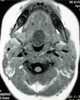

Lingual cyst